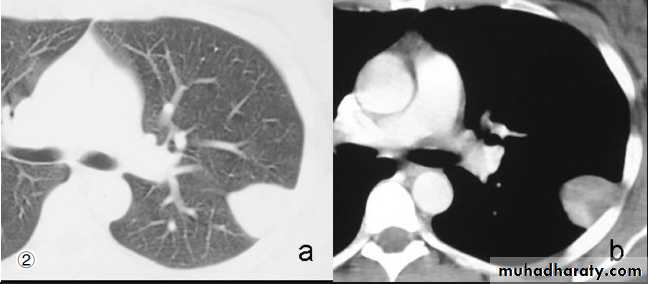

CT scan: IV CM part. Given when the purpose of examination is to visualize med., hila or pulm. Vessels.

Images usually viewed at both lung and med. Windows.

HRCT is thin section high spatial resolution CT, use for pulm. Parenchymal dis. And bronchiectasis.

1- presence and extent of med. Masses and other abn.: demonstrate LNs enlargement

Distinguish vascular from non vascular structure: e.g. mass from aneurysm.

NECT with lt. pulm. A. thrombosis2- Showing shape of intrapulmonary or pleural opacity, detecting calc. or cavitation when plain CXR not conclusive.

5- bronchiectasis.

Only structures seen normally in CT scan of chest are blood vs., fissures and walls of bronchi(as on CXR).

Fissures seen as line or as avascular zone